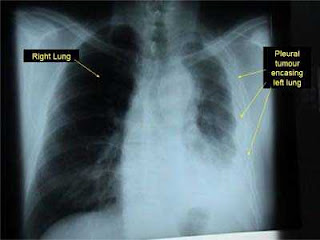

Symptoms of mesothelioma include shortness of breath due to pleural effusion (fluid between the lung and the chest wall) or chest wall pain, and general symptoms such as weight loss. Diagnosis can be suspected with chest X-rays and CT, and by examination of a biopsy (tissue sample) and microscopic confirmation. A thoraco scopy (inserting a tube with a camera into the chest) can be used to take biopsies.

Mesothelioma is a (cancer) benign (not cancerous) or malignant tumors mesothelium, the membrane that most of the internal organs of the body covered. Most cases ofmesothelioma at the beginning of the pleura (the lining around the lungs) or peritoneum(abdominal lining).

Benign mesothelioma can also be a fibroma and mesothelioma cancer known asmalignant mesothelioma. Mesothelioma can continue to be named, where it occurs. For example, malignant pleural mesothelioma cancer that begins in the lining around the lungs.